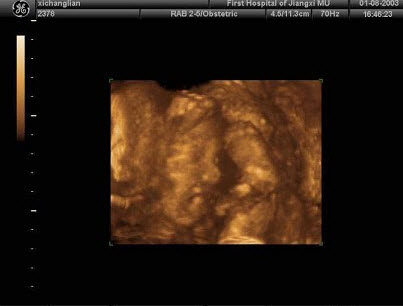

下图为宫内孕囊声像图,可见心管搏动,该胎儿至少大于多少周()

A.6周

B.9周

C.10周

D.12周

E.8周